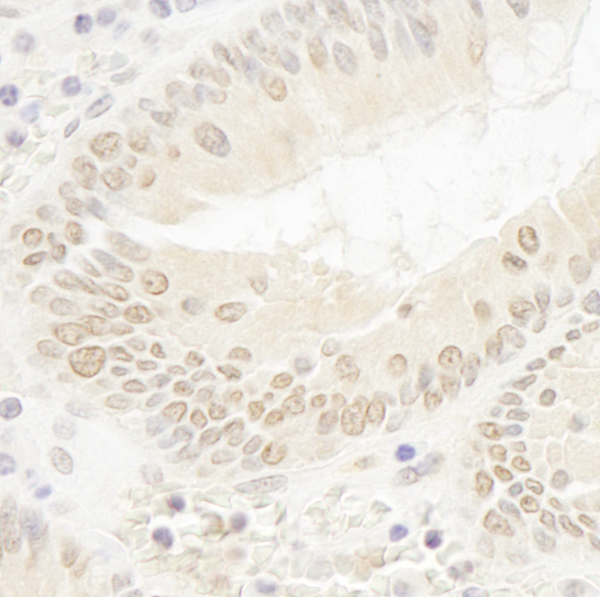

(Detection of human DOT1L by immunohistochemistry. Sample: FFPE section of human colon carcinoma. Antibody: Affinity purified rabbit anti-DOT1L (Cat. No. AAA214051) used at a dilution of 1:100. Detection: DAB)